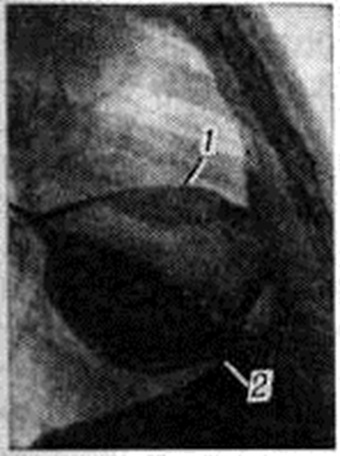

ИсторияСведения о возможности скопления выпота в плевральной полости имелись уже в древности. Так, в трудах Гиппократа (5—4 веков до нашей эры) и К. Галена (2 век нашей эры) упоминается об эвакуации гноя из плевральной полости с помощью разреза (прокола) грудной стенки. В 18 век Г. Ван-Свитен и другие начали выделять Плеврит в качестве самостоятельного патологический процесса. В начале 19 век в трудах Р. Лаэннека (1819—1821) были разработаны основы физикальной диагностики Плеврит, расширившие возможности его клинические, распознавания. Дальнейшее качественное развитие диагностика Плеврит получила на рубеже 19 и 20 веков в результате открытия и введения в практику рентгенологическое методов исследования органов грудной полости. Во время первой и второй мировых войн гнойные Плеврит (эмпиема плевры) являлись наиболее частым и тяжёлым осложнением проникающих огнестрельных ранений груди. В этот период начали детально разрабатываться методы лечения этого вида патологии плевры. Дальнейшее развитие эта проблема получила в результате быстрого развития лёгочной хирургии в послевоенные годы. СтатистикаСтатистика. Достоверных статистических данных, касающихся общей заболеваемости Плеврит и смертности от него, нет ни в отечественной, ни в зарубежной литературе. Это связано прежде всего с тем, что в подавляющем большинстве случаев Плеврит регистрируется под рубриками заболеваний, осложнением которых он является. Кроме того Плеврит часто протекает без выраженной клинические, симптоматики, маскируется проявлениями основного патологический процесса и не распознается вообще. О частоте Плеврит можно косвенно судить по частоте встречающихся во время аутопсии сращений в плевральной полости, поскольку они являются следствием перенесённого воспаления плевры. По данным Итиды (Ichida, 1936), сращения между висцеральной и париетальной плеврой во время вскрытий были обнаружены у 48% лиц, погибших от несчастных случаев и у 80,5% умерших от тех или иных заболеваний. На протяжении последних десятилетий относительная частота и значение Плеврит различного происхождения существенно менялись. По данным В. А. Равич-Щербо и В. М. Гольдфельда (1933) и Г. Р. Рубинштейна (1949), до середины 20 век самой частой причиной экссудативных Плеврит был туберкулёз. В дальнейшем в результате успехов в профилактике и лечении туберкулёза положение существенно изменилось. Так, по данным Метцель (Metzel, 1978), в 40,8% случаев причиной плеврального выпота явились злокачественные новообразования (карциноматоз, мезотелиома плевры), тогда как туберкулёзная этиология Плеврит была установлена лишь в 20,6% случаев. ЭтиологияПоскольку подавляющее большинство Плеврит является осложнением или проявлением различных, преимущественно лёгочных, заболеваний, этиологией Плеврит условно считают причину заболевания, которое привело к возникновению Плеврит С точки зрения этиологии все Плеврит можно разделить на инфекционные, (в том числе инфекционно-аллергические), то есть связанные с инвазией плевры возбудителями инфекции или аллергической реакцией плевры на субплеврально локализующуюся инфекцию, и не инфекционные, или асептические, при которых воспалительный процесс в плевре возникает без непосредственного участия патогенных микроорганизмов. Инфекционные Плеврит чаще всего вызывают те виды патогенных микроорганизмов, которые являются причиной острого или хронический воспаления респираторных отделов лёгких. Так, крупозная, или долевая, пневмония, вызываемая преимущественно пневмококком или его ассоциациями, при типичном течении, как правило, осложняется Плеврит, что дало основание назвать её плевропневмонией. Острые очаговые пневмонии, также имеющие в большинстве случаев кокковую природу, нередко осложняются Плеврит Частой причиной длительно текущих серозных и серозно-фибринозных Плеврит является туберкулёз. Туберкулёзный Плеврит встречается как самостоятельная клинические, форма туберкулёза, а также при очаговом, диссеминированном, инфильтративном туберкулёзе лёгких, туберкулёзе внутригрудных лимфатических, узлов и других проявлениях туберкулёзной инфекции. Туберкулёзный Плеврит часто развивается при первичном туберкулёзе лёгких (смотри полный свод знаний Туберкулёз органов дыхания) как одно из его проявлений. Этим объясняется более частое возникновение туберкулёзного Плеврит у лиц молодого возраста и подростков. Сравнительно редко туберкулёзный Плеврит представляет собой одно из проявлений системного туберкулёзного поражения серозных оболочек (полисерозит). Гнойный Плеврит (эмпиема плевры) может иметь чрезвычайно разнообразную этиологию, причём в качестве возбудителей на первое место выступают гноеродные кокки. По данным М. И. Кузина (1976), чаще всего возбудителем эмпиемы плевры является стафилококк (37%), несколько реже — стрептококк (27,2%) и грамотрицательные палочки (синегнойные палочки, протей и так далее— 23,9%), ещё реже — диплококки (6,5%). Особо тяжёлые эмпиемы, осложняющие гангрену лёгкого, могут обусловливаться анаэробной и гнилостной микрофлорой (анаэробные и гнилостные Плеврит). Известны Плеврит грибковой природы: при кокцидиоидомикозе, бластомикозе и других грибковых поражениях, а также паразитарные Плеврит, возникающие в результате прорыва в плевральную полость эхинококковой кисты и инвазии плевры другими паразитами, например, трематодами (Paragonimus westermani). Неинфекционные (асептические) Плеврит могут развиваться в результате кровоизлияния в плевральную полость (так называемый травматический Плеврит). Весьма часто встречаются Плеврит, связанные с карциноматозом плевры в результате диссеминации по поверхности плевры бронхогенного рака или раковых опухолей другой локализации, а также первичных опухолей плевры (мезотелиом). Экссудация в плевральную полость может сопровождать также системные заболевания соединительной ткани: ревматизм, системную красную волчанку, склеродермию, дерматомиозит, узелковый периартериит (смотри полный свод знаний Коллагеновые болезни). Часто плевральный выпот появляется при остром инфаркте лёгкого (смотри полный свод знаний) в результате тромбоэмболии ветвей лёгочной артерии. ПатогенезПатогенез плеврита находится в теснейшей зависимости от вызывающих его причин. У подавляющего большинства больных выпотным Плеврит решающую роль в развитии и течении заболевания играет изменённая реактивность — это Плеврит так называемый инфекционно-аллергической природы. В цепи патогенетических звеньев при Плеврит инфекционно-аллергического генеза можно условно выделить протекающий субклинически этап сенсибилизации плевры, во время которого наблюдается повторное поступление из очага инфекции в субплевральную зону лёгкого и плевру антигенов — микробов, продуктов их жизнедеятельности (токсинов), а также белковых и высокополимерных белково-полисахаридных комплексов, образующихся в результате повреждающего действия микробов на ткани и изменённого тканевого обмена. К антигенам (смотри полный свод знаний) вырабатываются и накапливаются соответствующие антитела (смотри полный свод знаний). В результате встречи в сосудистом русле и соединительнотканной основе плевры антигенов и антител образуется большое количество биологически активных веществ: гистамина (смотри полный свод знаний), серотонина (смотри полный свод знаний) и другие Вместе с продуктами изменённого обмена они вызывают местные нарушения кровообращения, повреждение эндотелия сосудов, что ведёт к повышению проницаемости сосудистой стенки (смотри полный свод знаний Проницаемость), образованию выпота и повреждению слоистых бессосудистых структур плевры, играющих роль тканевого барьера. Таким образом, повреждение сосудов и соединительнотканной основы висцеральной плевры приводит к развитию экссудативного плеврита. Одновременно с экссудацией наблюдается выпадение фибрина в толще и на поверхности плевры. В других случаях, например при гнойных Плеврит, явно преобладает непосредственное воздействие микробов, обсеменяющих плевру. Пути проникновения возбудителей инфекции в плевральную полость при Плеврит инфекционного генеза различны. Непосредственное инфицирование плевры происходит из субплевральных патологический очагов. По мнению С. И. Спасокукоцкого (1938), инфицированию плевральной полости гноеродными микроорганизмами практически всегда предшествует прорыв в плевральную полость субплеврального гнойного очага. Переход воспалительного процесса с лёгочной ткани на плевру может происходить лимфогенно (лимфогенный Плеврит), что, по мнению Д. А. Жданова (1946) и Плеврит А. Теппера (1952), осуществляется так называемый ретроградным, или центробежным, током тканевой жидкости, который может выносить возбудителей инфекционного воспаления из глубины лёгкого в плевральную полость. Распространение возбудителей инфекции из субплевральных патологический очагов гематогенным путём (гематогенный Плеврит) наблюдается значительно реже. Прямое попадание возбудителей инфекции в плевральную полость со стороны раны грудной стенки или со стороны инфицированной лёгочной ткани и воздухоносных путей, целость которых может нарушаться, имеет место в хирургической практике при ранениях груди и оперативных вмешательствах. Для туберкулёзных Плеврит характерным является инфицирование плевры микобактериями из поражённых туберкулёзным процессом бронхолёгочных лимфатических, узлов, субплевральных очагов или же в результате прорыва в плевральную полость каверн с формированием пиопневмоторакса (смотри полный свод знаний). В основе плевральной экссудации при неинфекционных Плеврит также лежит повышение тканевой и сосудистой проницаемости субплевральной зоны лёгких и самой плевры. Развитие травматических Плеврит связано с воспалительной реакцией плевры на излившуюся в плевральную полость кровь. При малоизменённых плевральных покровах и небольшом объёме гемоторакса (смотри полный свод знаний) излившаяся кровь остаётся в жидком состоянии или же образовавшийся вначале сгусток лизируется. В этом случае при отсутствии инфицирования кровь как бы разводится плевральным выпотом, эритроциты постепенно разрушаются, а богатый гемоглобином жидкий выпот медленно всасывается, оставляя впоследствии относительно небольшие сращения. Травматический гемоторакс, особенно при значительном разрушении тканей грудной стенки и лёгкого, сопровождающийся освобождением большого количества тканевых факторов свёртывания, обычно приводит к формированию массивного, не подвергающегося фибринолизу сгустка, который при асептическом течении Плеврит подвергается медленной организации с формированием плотных шварт, ограничивающих функцию лёгкого. Плевральный выпот при карциноматозе плевры возникает, с одной стороны, под воздействием на плевру продуктов патологический обмена, выделяемых опухолью, с другой — в результате блокады метастазами путей оттока лимфы в области корня лёгкого и средостения, а также блокады устьиц и люков париетальной плевры (смотри полный свод знаний Плевра) вследствие диссеминации опухоли по плевре, а также деструкции серозных покровов плевры при развитии или при прорастании опухоли из подлежащих тканей. Появление в плевральной полости геморрагического выпота при деструктивном панкреатите связано с лимфогенным проникновением в плевральную полость активных ферментов поджелудочной железы, в большом количестве обнаруживаемых в плевральном выпоте. В образовании, накоплении и последующем рассасывании плеврального выпота при Плеврит различной этиологии имеет значение взаимодействие трёх факторов: воспалительной экссудации из висцеральной плевры, давления в плевральной полости и способности оставшихся неизмененными отделов париетальной плевры к резорбции. Торможение процесса всасывания выпота в разгар экссудации связано со сдавлением лимфатических, сосудов париетальной плевры и нарушением их функций, закрытием устьиц и люков между мезотелиальными клетками выпадающим фибрином, нарушением дыхательных экскурсий лёгкого, играющих роль насоса, и ослаблением работы смещённого выпотом сердца. При определённых условиях, например обсеменении плевры туберкулёзными бугорками, проникновении гнойной или гнилостной инфекции, процессы экссудации и резорбции могут быть нарушены на длительное время. При обратном развитии патологический процесса, вызвавшего появление Плеврит, жидкая часть выпота постепенно резорбируется, фибринозные наложения подвергаются организации соединительной тканью с образованием шварт и сращений, частично или полностью облитерирующих плевральную полость. Однако гнойный выпот ни при каких обстоятельствах самостоятельно резорбироваться не может, его элиминация из плевральной полости возможна только в результате прорыва наружу через грудную стенку, в бронхи или же в результате лечебных манипуляций (эвакуация с помощью пункции или дренирования). Патологическая анатомияСухой (фибринозный) Плеврит характеризуется отсутствием свободного жидкого выпота в плевральной полости. Поверхность плевры тусклая, покрыта тонкой сероватой плёнкой или хлопьевидными массами фибрина (смотри полный свод знаний), которые в первые дни легко, а позже, когда начинается организация, трудно снимаются с её поверхности. К фибрину в том или ином количестве примешиваются макрофаги (смотри полный свод знаний), плазматические клетки (смотри полный свод знаний), лимфоциты (смотри полный свод знаний), гранулоциты. В процессе организации фибрин рассасывается и замещается соединительной тканью, что приводит к фиброзному утолщению плевры. Для исхода фибринозного Плеврит типично развитие спаек и синехий, которые носят тяжевидный, плёнчатый или плоскостной характер, богато васкуляризированы, иннервированы, нередко содержат сосуды замыкающего типа и не связанные с сосудами пучки гладких мышечных волокон. Фиброзная ткань в спайках чередуется с прослойками жировой ткани, иногда подвергается гиалинозу, петрификации. В редких случаях после фибринозного Плеврит в плевральной полости остаются так называемый фибринозные тела — круглые или овальные образования из фибрина. Серозный Плеврит встречается редко, чаще он сопровождается небольшим выпотом фибрина и носит серозно-фибринозный характер. Серозно-фибринозный Плеврит микроскопически характеризуется расширением кровеносных и лимфатических, сосудов плевры, иногда тромбозом, повышением проницаемости их стенки для лейкоцитов и макрофагов, которые вместе с жидкой частью выпота проникают в плевральную полость. Мезотелий плевры слущивается, и она приобретает тусклый вид. Если примесь фибрина велика, возникает плёнка, более толстая в базальных отделах, где иногда на ней образуются ворсинки вследствие слипания париетальной и висцеральной плевры во время дыхательных экскурсий. Плевральный выпот имеет вид мутной жидкости жёлтого цвета с хлопьями фибрина. Удельный вес выше 1,016; в осадке лимфоциты, гранулоциты, макрофаги, слущённые клетки мезотелия. Серозно-фибринозный Плеврит, возникающий при различных заболеваниях, имеет некоторые особенности в каждом конкретном случае. Ревматический Плеврит помимо серозно-фибринозного выпота характеризуется мукоидной, фибриноидной дистрофией коллагеновых волокон плевры. При аллергических заболеваниях в выпоте находят большое количество эозинофилов (эозинофильный Плеврит). При прорастании средостения опухолью при лимфогранулематозе в выпоте появляются липиды, проникающие в плевральную полость через стенку лимфатических, сосудов плевры, проходимость которых нарушается вследствие блокады их опухолью или сдавления увеличенными лимфатических узлами. Выпот и поверхность плевры при этом приобретают опалесцирующий характер. При раке лёгкого и опухолях другой локализации (раке молочной железы, желудка) нередко развивается геморрагический Плеврит, для которого характерно скопление в плевральной полости мутноватого кровянистого выпота, содержащего большое количество эритроцитов, а также клетки опухоли. Наблюдается резкая гиперемия плевры, кровоизлияния на её поверхности; кроме этого, нередко развивается раковый лимфангиит. Лимф, сосуды, нафаршированные раковыми клетками, приобретают вид белесоватых шнурков, выступающих на поверхности плевры (рисунок 2). Иногда плевра обсеменяется мелкими метастазами.